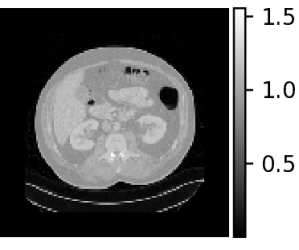

| Density map (g/cc) | Organ dose map (mGy) | |

Axial |

![]() |

|

Sagittal |

Coronal |

For individualized patient organ dose, patient CT images were used to generate patient-specific voxelized phantoms that contain spatial maps of both material type and mass density. The CT images were first resampled to isotropic voxels of mm3 to keep the computational demands reasonable. The density mapping was performed following a piece-wise linear curve which defines the densities of the mixture of water and bone [45]. Figure 5 visualizes the MC-GPU inputs of mass density and corresponding material map in different views (axial, sagittal, coronal) of a patient CT scan.

We simulated a helical scan from the most superior to most inferior slice for the geometry of a GE Revolution CT scanner. Table 1 lists the modified set of parameters for our MC-GPU configuration. We repeated the MC-GPU dose simulation with uniformly spaced apart start angles . Considering the actual start angles cannot be controlled prospectively, therefore, we averaged the dose maps to obtain the dose map [41].

where, is the voxelized phantom and denotes the set of all the parameters used to configure the MC-GPU simulation. MC-GPU dose is reported as eV/g/photon and was scaled to the more standard mGy for a 100 mAs scan with constant tube current, using a scanner-specific calibration to convert a simulated 32 cm CT dose index (CTDI) phantom to a physical CTDI measurement (1 eV/g/photon = 1.8143 mGy/100 mAs). Figure 5 visualizes a representative dose map. Using a threshold g/cc in the voxelized phantom, we masked out the air and obtained the patient body dose map. Therefore, from average dose map in (2), the final dose map is obtained as

An example patient CT density map and the corresponding organ dosemap (segmented organ contours overlaid on the dosemap) at three different views obtained from the modified MC-GPU tool can be seen in Figure 5. Moreover, Figure 6 shows the distributions of organ and patient body doses for all the patient CT scans.